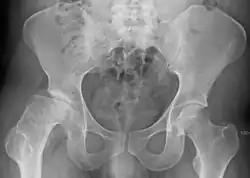

![]() | |

| Radiograph of a person with Legg–Calvé–Perthes disease | |